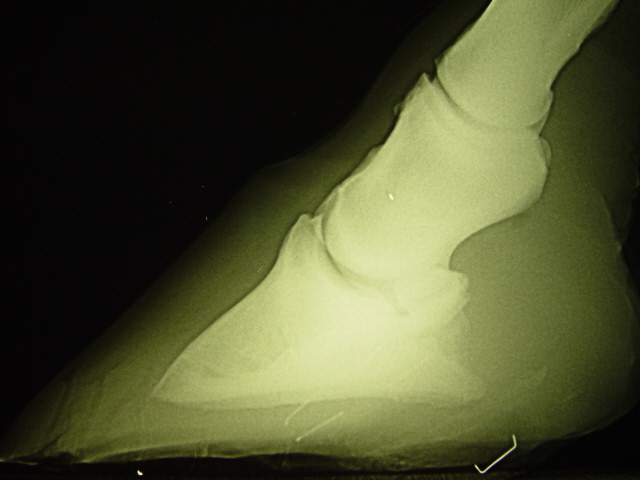

Seitliches Röntgen

Atrophie der Hufbeinäste bei horizontalem Hufbeinwinkel, Deformation der Hufbeinspitze